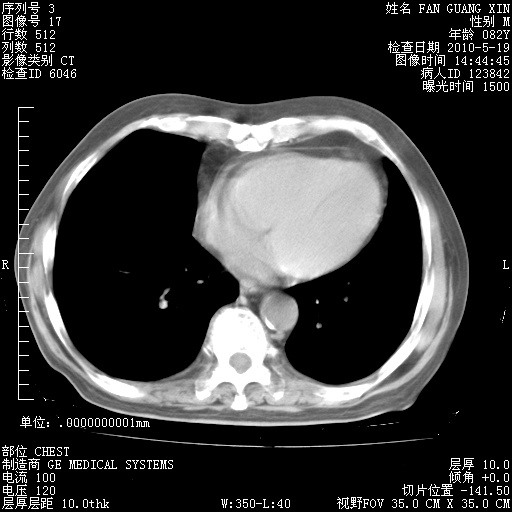

复查肺部CT,明显好转。为什么发热呢?

治疗3周后的肺部CT

治疗3周后的肺部CT纵隔窗